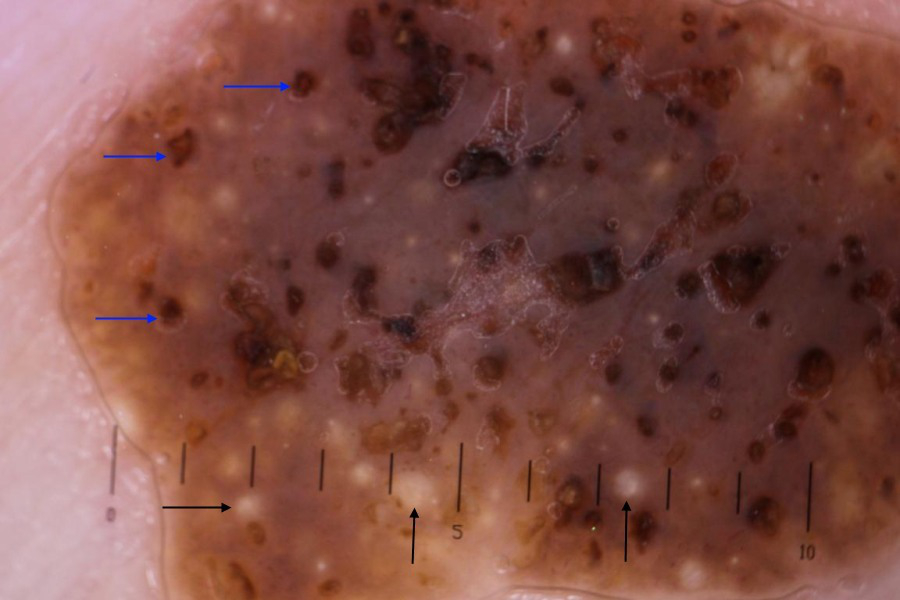

Algoritmos de aprendizagem automática estão sendo investigados para fins de classificação de lesões cutâneas pigmentadas (inclusive o diagnóstico de ceratose seborreica), e os estudos iniciais são promissores, mas essa modalidade ainda não está sendo amplamente usada na prática clínica.[25] Os elementos dermatoscópicos característicos da ceratose seborreica são cistos similares à milia e aberturas semelhantes a comedões. Cistos semelhantes à milia são estruturas redondas brancas ou amareladas que correspondem a pequenos cistos intraepidérmicos preenchidos com queratina (pérolas córneas). Eles não são encontrados exclusivamente na ceratose seborreica, pois também são observados nos nevos congênitos e nos nevos dérmicos papilomatosos, mas com menos frequência.

Aberturas semelhantes a comedões (também conhecidas como aberturas pseudofoliculares ou criptas) são orifícios amarronzados na superfície da ceratose seborreica, que correspondem histologicamente a invaginações preenchidas com queratina da epiderme.[7][26] São critérios dermatoscópicos adicionais uma superfície girata (aparência semelhante a um cérebro) e vasos enrolados.[Figure caption and citation for the preceding image starts]: Imagem dermatoscópica de ceratose seborreica no tóraxDo acervo do Dr. Braun e do Dr. Kolm, usado com permissão [Citation ends].

[Figure caption and citation for the preceding image starts]: Aparência dermatoscópica típica de ceratose seborreica com cistos similares à milia (setas pretas) e aberturas semelhantes a comedões (setas azuis)Primary Care Dermatology Society (PCDS); usado com permissão [Citation ends].